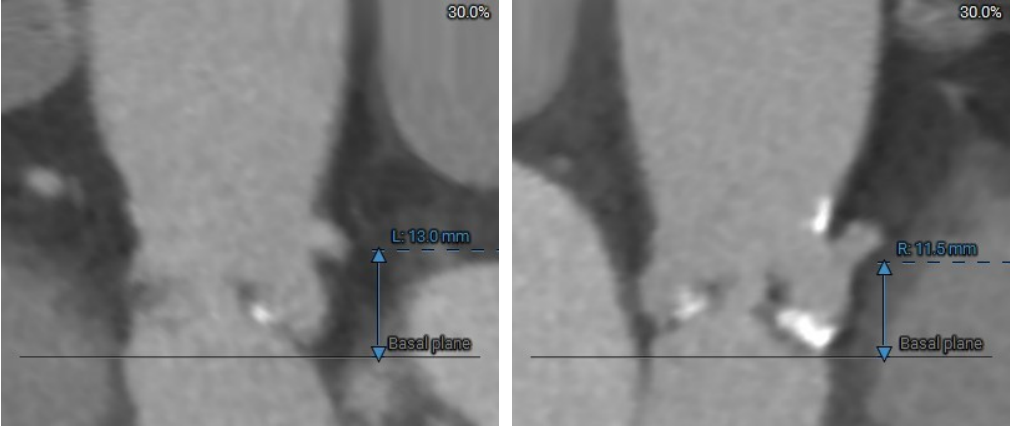

CT评估

收缩期瓣环:70.3mm

收缩期流出道:72.2mm

舒张期瓣环:68.1mm

舒张期流出道:73.1mm

左冠高度10.8mm

右冠高度14.1mm

主动脉窦宽:32.8mm、31.3mm、32.4mm

窦管结合部:113.9mm

升主动脉:146.6mm